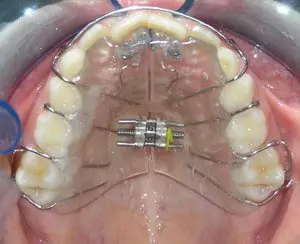

These are the mini Retention used with orthodontic braces for moving teeth. They are used when malocclusion is severe or there is severe crowding of teeth. This helps in accurate and faster orthodontic treatment with precision.

Expansion appliances increase the width of the jaws to broaden the smile and to prevent the extraction of permanent teeth. These appliances work best before all of the permanent teeth erupt.